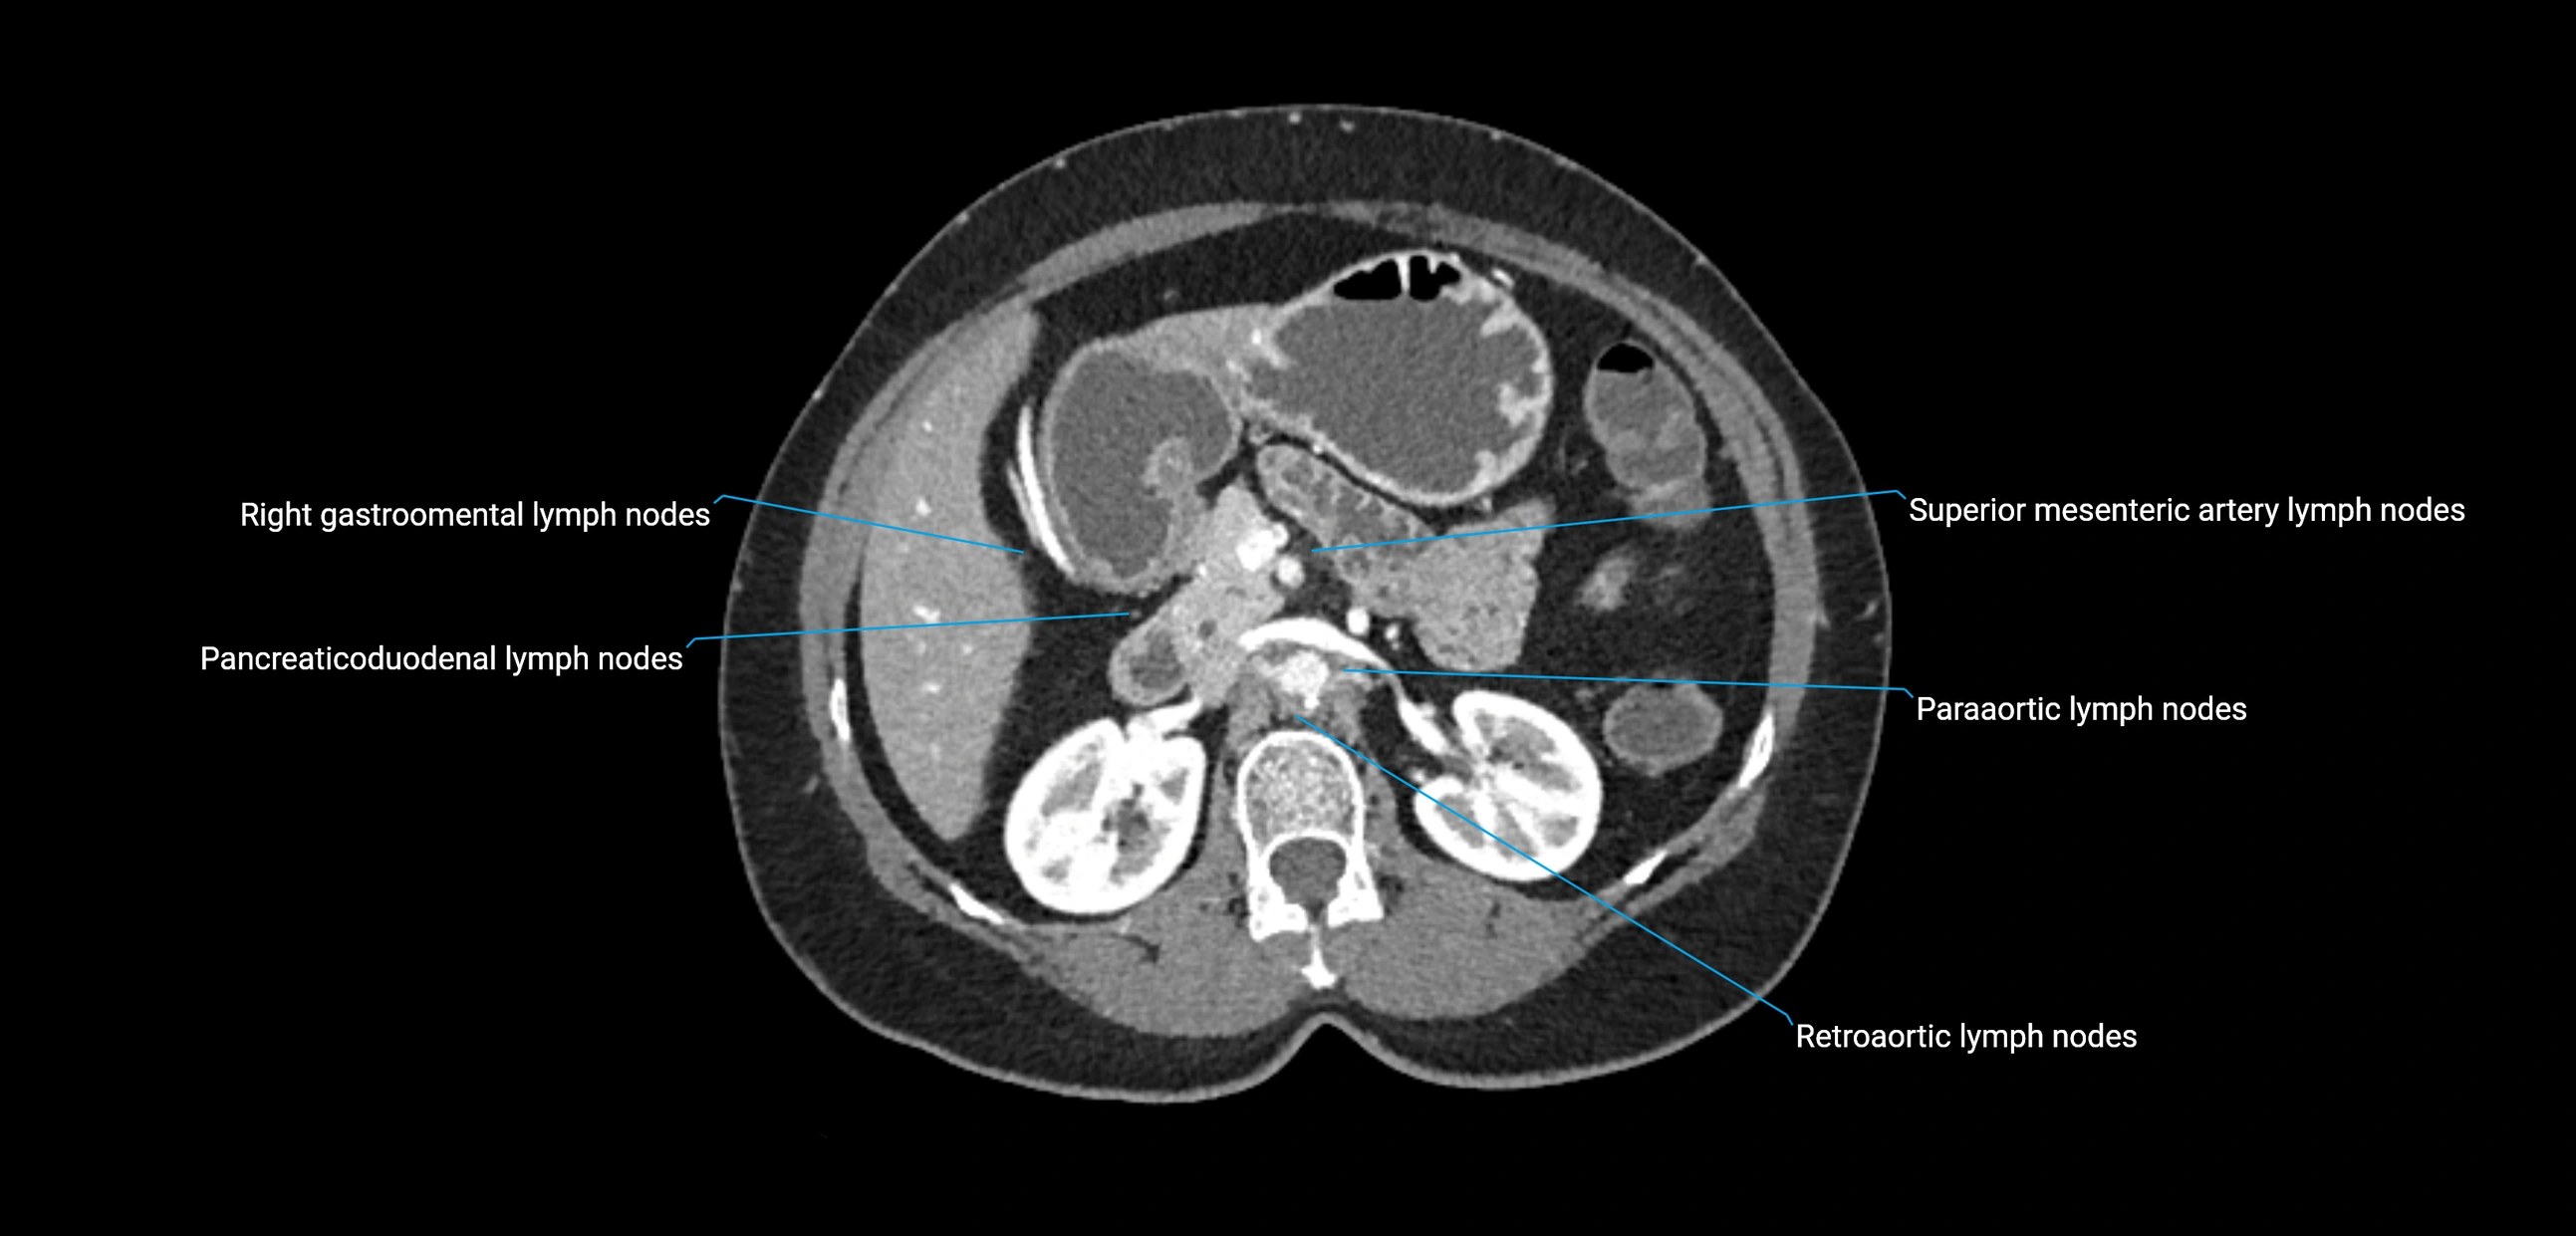

CT Appearance

CT Pre-Contrast:

• Nodes appear as soft-tissue density nodules adjacent to the aorta and IVC

• Calcification may be seen in chronic infections (e.g., tuberculosis)

CT Post-Contrast:

• Normal nodes enhance homogeneously

• Malignant nodes may show heterogeneous enhancement, central necrosis, or conglomerate formation

• Size >1 cm short axis is suspicious, though morphology and distribution are equally important

CT Venography (CTV):

• Demonstrates nodal encasement or compression of adjacent vessels (aorta, IVC, renal veins)

• Useful in staging testicular and ovarian malignancies

• Provides 3D reconstructions for retroperitoneal lymph node dissection planning